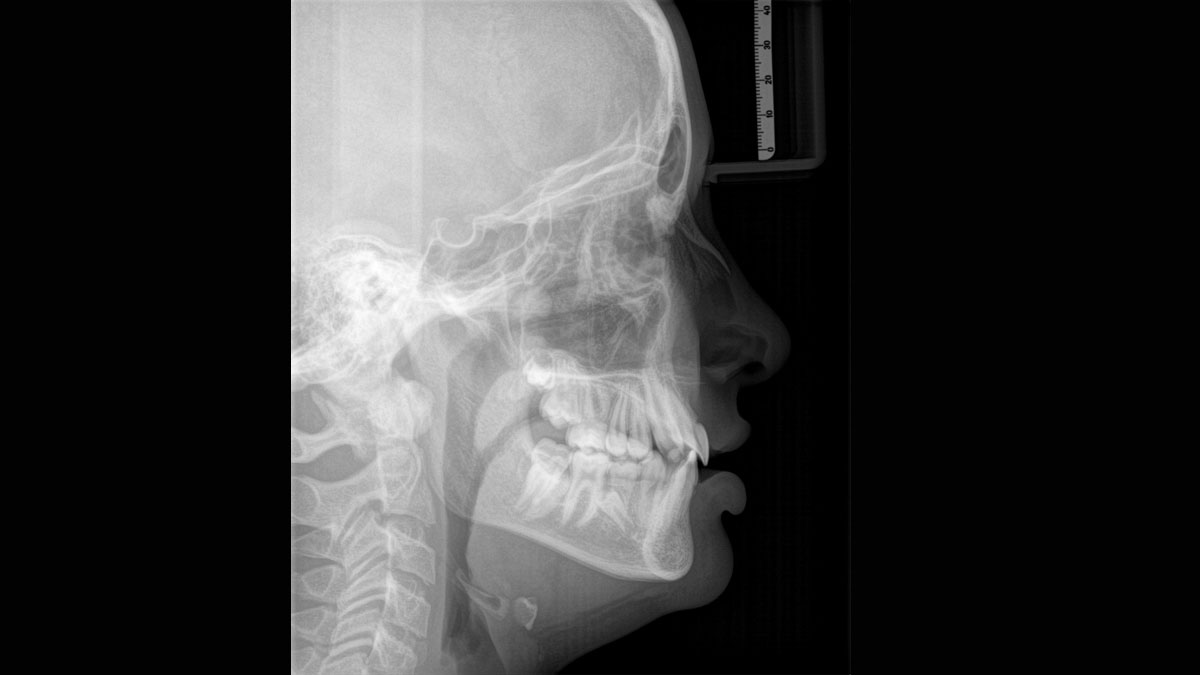

Para obtener imágenes panorámicas excepcionales con alta nitidez. Puede elegir un brazo cefalométrico derecho o izquierdo opcional, que puede reacondicionarse en cualquier momento

El sensor de conversión directa (Direct Conversion Sensor, DCS) ha revolucionado el estándar de la imagen panorámica. Las imágenes radiológicas se convierten directamente en señales eléctricas. Por lo tanto, no hay pérdida de señal debido a conversión de la luz, como es el caso de los sistemas convencionales. El resultado: imágenes con un alto nivel de nitidez y contraste, incluso con una dosis de radiación extremadamente baja. Para obtener información de diagnóstico precisa a fin de apoyar el tratamiento objetivo.

La imagen a continuación muestra una radiografía panorámica con y sin tecnología DCS. Usando la flecha, arrastre el control a través de la imagen para ver la diferencia que el sensor de conversión directa hace con la calidad de la imagen y las posibilidades de diagnóstico.